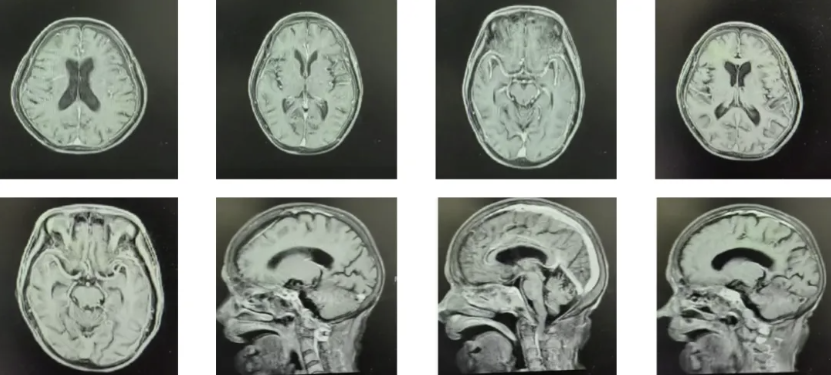

图1 我院12.15胸部CT增强对比旧片

患者双肺散在多发结节灶,左肺下叶外基底段见一较大结节灶(2.4cm×1.7cm),边界尚清,增强扫描呈不均匀明显强化,邻近胸膜增厚。余双肺见多发小结节(大者约0.6cm×0.6cm),界清,部分于纵隔窗显示,增强扫描呈不均匀强化。双肺可见散在网格状、蜂窝状、斑片状及条索状密度增浓影,边界较清。双肺部分支气管管壁增厚,以右肺为著。双肺门区及纵隔内见多发稍大淋巴结,部分伴钙化(大者短径约1.0cm)。双侧胸膜稍增厚,双侧胸腔少量积液。扫及主动脉壁、冠状动脉壁可见钙化灶。左侧第9肋骨腋段部分骨皮质不连;胸7椎体变扁呈楔形。扫及双乳见散在钙化斑点,双肾散在小斑点状致密影。甲状腺密度不均,其内可见结节状稍低密度灶。肝内多发类圆形低密度灶(大者径约2.2cm),部分呈轻度强化。双侧肾上腺各见一结节(大者径约1.1cm),增强扫描呈轻度强化。腹腔少量积液。

林棱主任医师:该病例的影像学演变非常值得深究。患者9月份PET-CT显示双肺病灶SUVmax仅2.03,纵隔淋巴结SUVmax 3.63,当时确实倾向于炎性病变。但3个月后左肺结节从1cm迅速增大到2.4cm,这种倍增速度符合肿瘤生长规律,而非感染性疾病。需要警惕PET-CT在部分低度恶性淋巴瘤或黏液腺癌中的假阴性,因其FDG摄取可能不高。此外,全身多发钙化灶(肺、胰腺、淋巴结)需考虑两点:一是是否为陈旧性结核钙化,但患者TB-SPOT阴性,无结核中毒症状,钙化灶稳定不支持活动性结核;二是需警惕肿瘤相关的营养不良性钙化,特别是淋巴瘤可能。关于中枢受累,患者有淡漠、定向力障碍,虽颈软无抵抗,但老年颅内感染脑膜刺激征常不典型。脑脊液检查是必需的,但需警惕血小板重度低下带来的操作风险。目前三系减低不能以单纯感染解释,需高度怀疑骨髓浸润或噬血细胞综合征。

李鸿茹主任医师:垂体功能低下的原因需要重点甄别。患者皮质醇和ACTH同步降低,提示继发性肾上腺皮质功能减退。垂体MRI未见异常,席汉综合征诊断存疑——该综合征多见于产后大出血,79岁女性无相关病史。我更倾向于肿瘤相关性内分泌异常:一是淋巴瘤直接侵犯垂体,但影像学未显示;二是肿瘤分泌的细胞因子(如IL-6、TNF-α)抑制下丘脑-垂体轴,称为肿瘤相关肾上腺皮质功能不全。此外,患者有低钠血症,还需鉴别抗利尿激素分泌异常综合征(SIADH),这在肿瘤中常见。胸部增强CT是必要的,可观察结节血供及强化模式,肺癌转移与淋巴瘤的影像学特征不同:前者多为 solitary nodule with spiculation,后者多为 multiple nodules with ground-glass halo sign。建议尽快在风险可控前提下获取肺组织活检。

2025-12-15(入院第15天):复查胸部CT示左肺下叶结节较前明显增大(2.4cm×1.7cm),双肺新增多发结节,部分MT可能。全腹彩超:轻度脂肪肝,胆囊壁增厚,胆总管上段扩张并结石,双肾多发结石,腹腔积液。